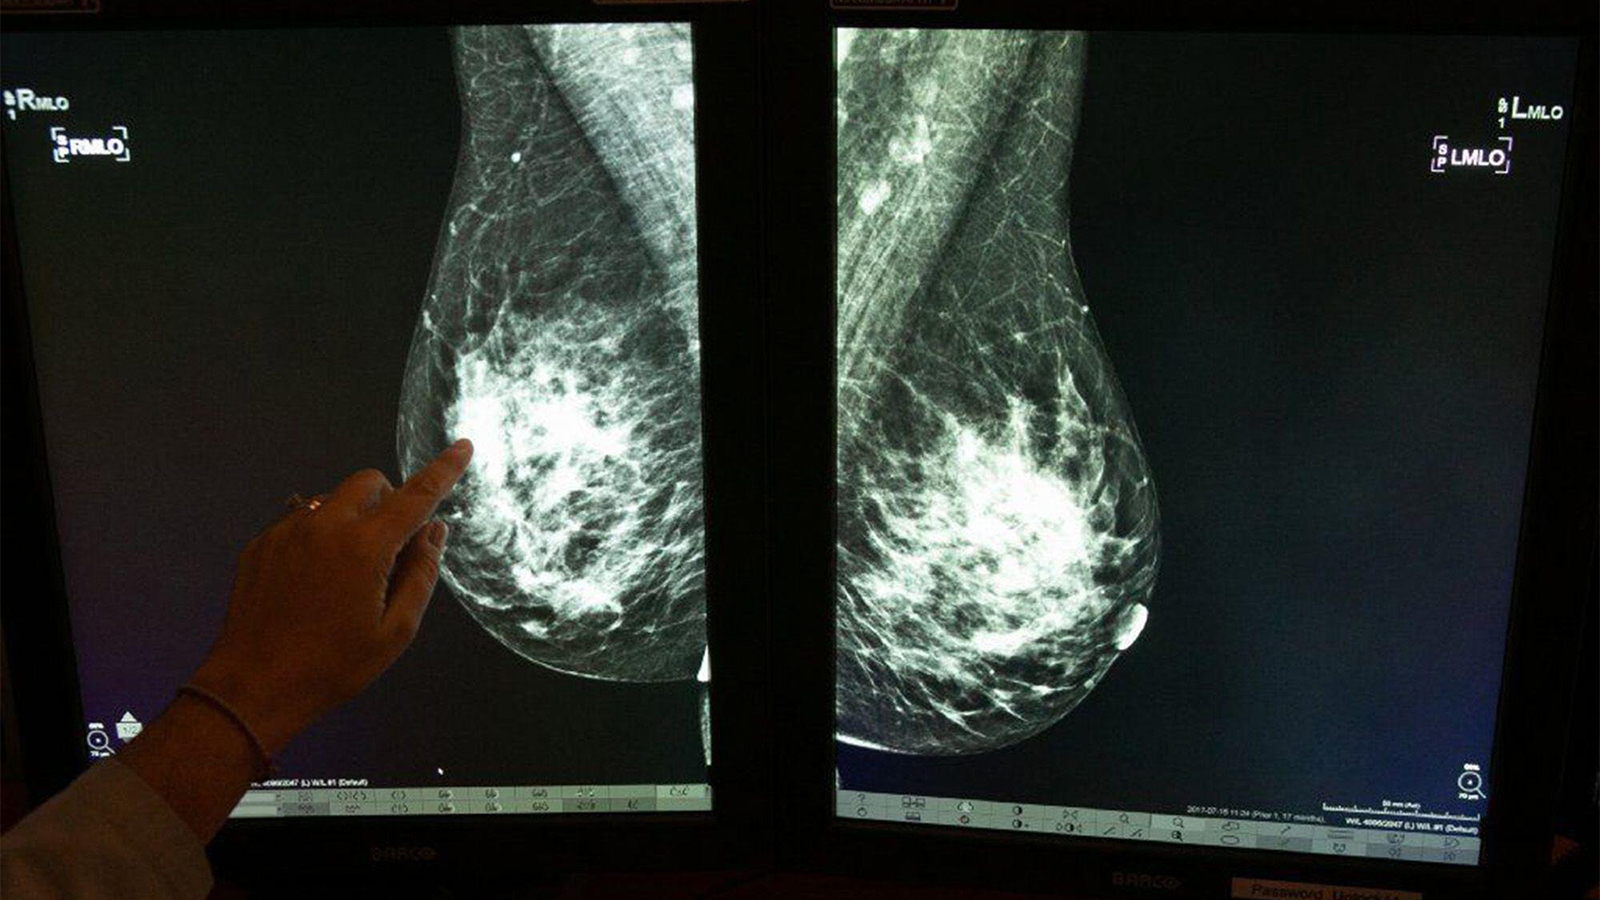

What Our Patients With Dense Breasts Deserve to Know

(MedPage Today) — Nearly half of all women have dense breasts, which increases their risk for breast cancer and means that mammograms may not work as well for them. While many women already know this information about their bodies, starting next…